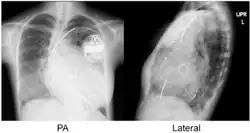

Estudios de imagen

La ecografía es usada comúnmente para apoyar el diagnóstico clínico de la insuficiencia cardíaca. Esta modalidad usa el ultrasonido para determinar la porción de sangre que entra al corazón que es expulsada con cada latido, es decir, la fracción de eyección. La ecocardiografía puede también identificar una anomalía en una válvula cardíaca y verificar el estado del pericardio que rodea al corazón. Adicional a ello, la ecocardiografía puede ayudar a determinar el curso de tratamiento a seguir para aliviar al paciente, tal como medicamentos, la inserción de un desfibrilador implantable o la terapia de resincronización cardíaca.[17]

La radiografía de tórax con frecuencia puede asistir en el diagnóstico de una IC. En el paciente compensado, puede mostrar cardiomegalia (agrandamiento visible del corazón), cuantificada como la proporción del tamaño del corazón en el pecho. En la insuficiencia cardíaca izquierda puede haber evidencia de redistribución vascular, líneas de Kerley, pérdida de definición bronquial y edema intersticial.[18]